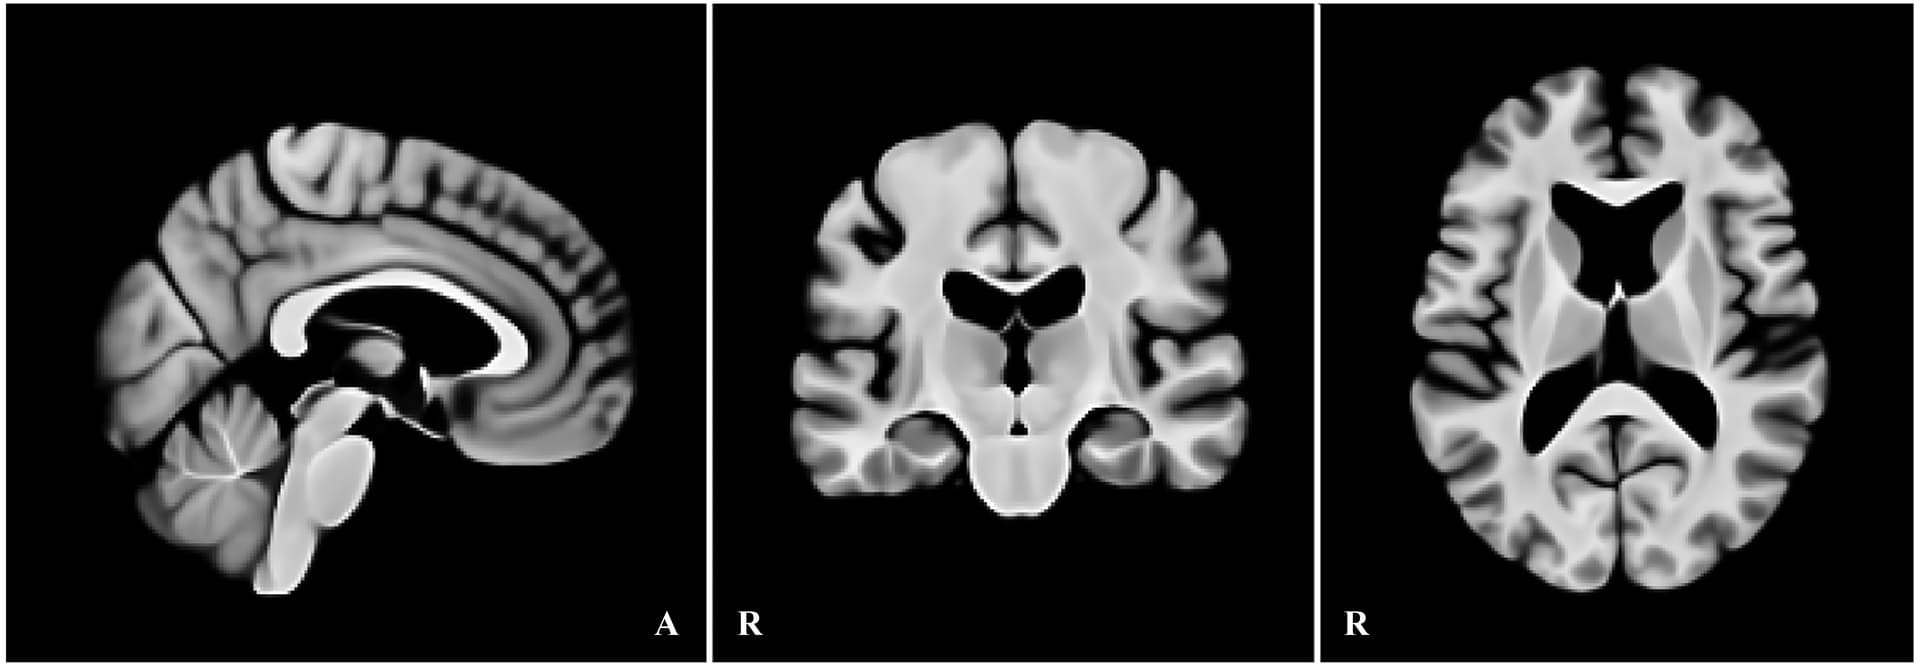

We publicly release an age-specific 1-mm T1 template for older adults (65+), together with

binary masks (GM/WM/CSF; brainstem, amygdala, caudate, hippocampus, pallidum, putamen, thalamus).

- T1w template (176×208×176; L–R, P–A, I–S; qform/sform = Scanner Anat)